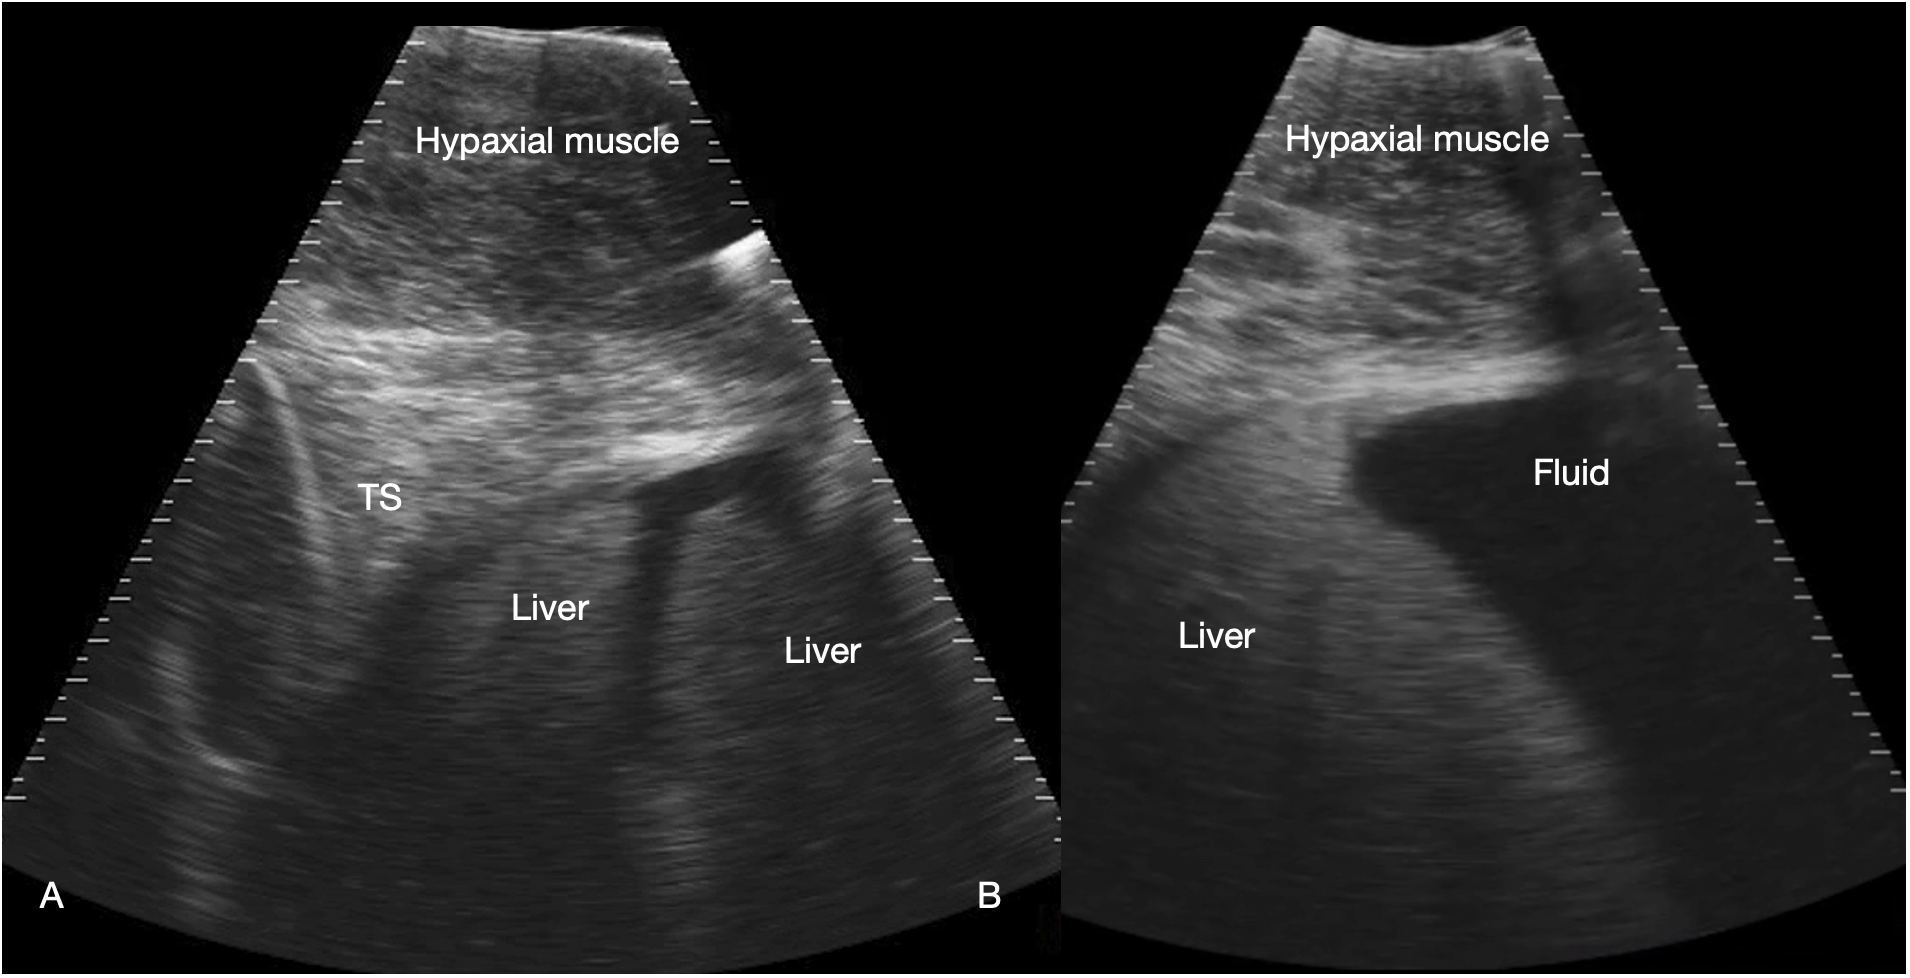

Figure 3

Liver. Sagittal sonograms of shark 31 at the pectoral line (A) and caudal to the pectoral line (B) showing the transverse septum (TS), liver and peritoneal fluid. Image displayed depth 21 cm, left of the image is cranial. See Supplementary Video S2.

Liver

The liver was recognized by its characteristic shape and sonographic appearance of finely granular parenchymal texture that was generally hyperechoic, becoming hyperattenuating in some individuals. This is consistent with hepatic sonographic appearance in other species with increasing lipid content causing attenuation of the ultrasound beam (Mattoon et al., 2020). The liver was visible from the pectoral girdle to a point caudal to the pelvic fins. The entire liver was not imaged in each animal due to limitations of access and compliance. At the cranial extent there were curved, convex margins that conformed to the transverse septum surface (Figure 3). The lobes were separated by a moderate volume of nearly anechoic peritoneal fluid. In the cranial portion, the lobar margins were triangular in transverse section, with slightly rounded margins. In the mid and caudal abdomen, the liver was positioned in the dorsolateral cavity and was seen as a strap-like, smoothly marginated structure with some occasional internal, tubular anechoic structures (venous sinus likely but not confirmed). The gallbladder was identified on and just to the right of midline, immediately caudal to the pectoral girdle (Figure 4). It was a large, elongated oval structure with a thin wall and anechoic fluid contents. When distended (up to 7.5 cm diameter), it folded on itself and was separated from the adjacent liver by anechoic peritoneal fluid. Dorsal and caudal to the gallbladder a broad tubular structure 2 – 3.5 cm in diameter was identified, coursing caudally in the sagittal plane, consistent with the common bile duct. Dorsal to the gallbladder was a cluster of thin-walled, fluid filled tubes. These may be tortuous bile duct or hepatic portal vascular structures, or a combination of both.